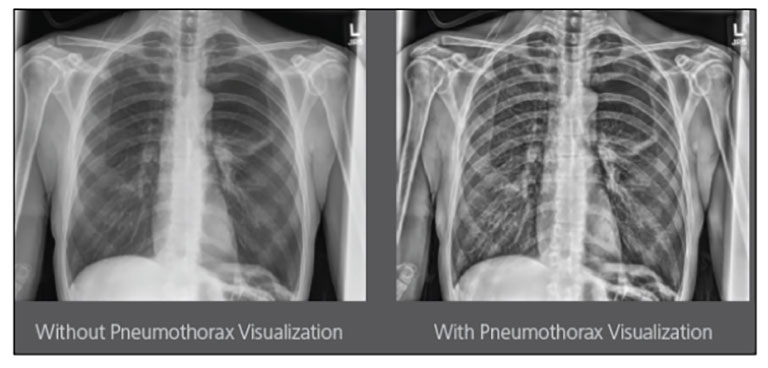

Carestream Introduces New Software Update to Boost Diagnostic Accuracy

Carestream today announced the latest update to its Image Suite V4 Software, MR 11: a series of enhancements to help improve customer confidence and increase diagnostic accuracy [...]

Our Carestream Focus HD 35/43 Retrofit Detectors, powered by Image Suite Software, are an ideal solution to step up to full digital X-ray for customers who simply cannot compromise on image quality. It seamlessly integrates into existing setups, bringing the power of full digital X-ray with minimal disruption and maximum clarity, along with the following benefits: